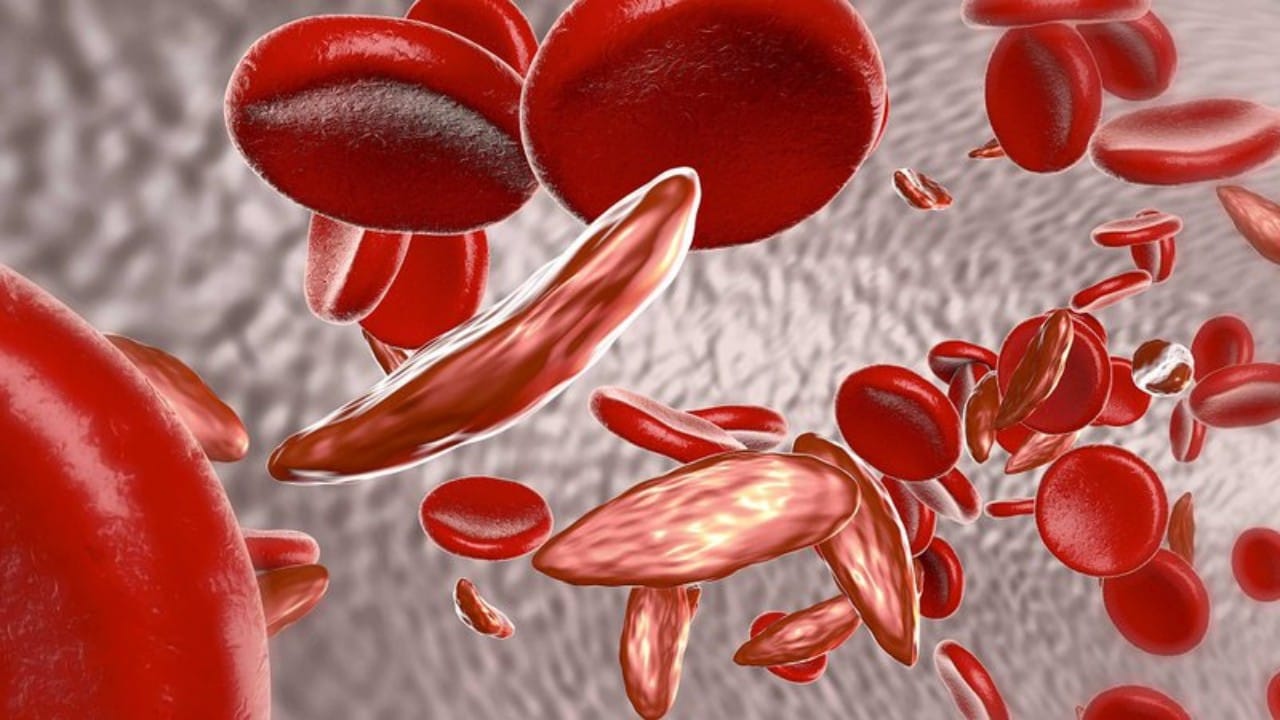

أعراض مرض الثلاسيميا والعلاجات المستخدمة لمواجهته